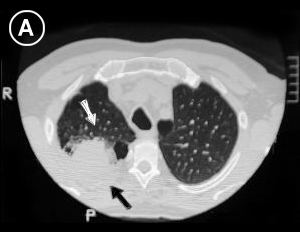

Corte Tomográfico

en tercio superior del tórax:

• Flecha Blanca: Lesión tumoral de bordes irregulares, redondeada, sólida, intraparenquimatosa.

• Flecha Negra: Lesión tumoral mal definida en su parte posterior, engrosamiento pleural, pequeña bula enfisematosa, no se aprecia la estructura ósea del 3er. arco costal posterior.